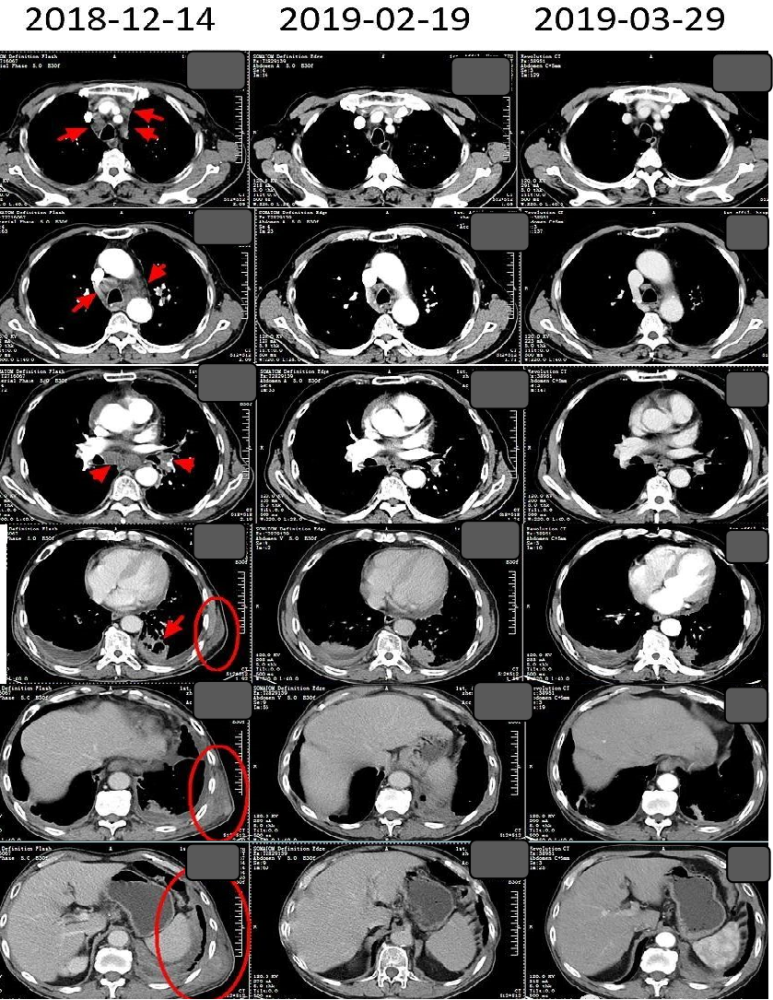

肺癌病例73岁晚期肺腺癌生存期接近4年

图片尺寸1008x703

3疗程新辅助治疗后肿瘤明显缩小替雷利珠单抗联合化疗使局部晚期肺

图片尺寸949x390